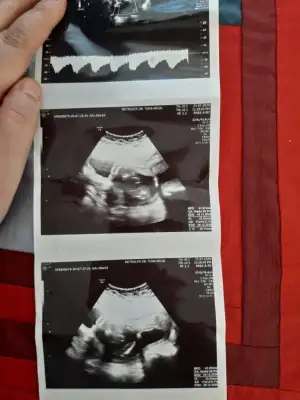

Erkek gibi 12-13 hafta olursa tekrar usg paylaşınBenimkini de tahminde bulunabilecek var mı 11. Hafta :))

TeşekkürlerErkek gibi 12-13 hafta olursa tekrar usg paylaşın![]()

Sadece resmi paylaşın tahminini yazmayın bakalım tutturacammıTeşekkürler2 hafta sonra randevumuz var doktorun tahmini olursa burda resmî ve tahmini de paylaşıcam